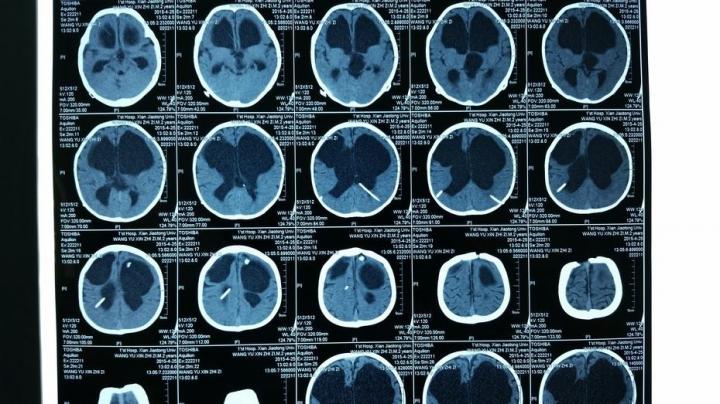

【CT:扫描更具立体感,分辨率更高】

CT正是在这样的医学背景下被研发。CT根本的检查和成像原理与X光相同,但二者最根本的区别在于,X光是将人体的一个或者多个器官投射到同一个平面上进行成像;CT是将人体的一个器官或者多个器官进行一层一层的扫描。

要解释这一点首先还是让我们从“CT”这个名称入手。“CT”的中文全称为“电子计算机断层扫描”。这个所谓的“断层扫描”可以这样理解,在人体的患病部位截取一个长方体,然后再把这个长方体依据不同的层厚与层距分为若干个小长方体进行分别扫描。

这项技术相比X光的突破在哪里呢?X光把前后重叠的肌肉、骨骼、器官全部投射到同一个平面上成像,这就涉及到相互遮挡等问题。这就像你要看一个人的背影,可只有一张正面的照片一样。所以X光的拍摄当中,有患者经常碰到医生要求从不同角度拍摄。

(图)脑部CT片

从X光到CT的突破和进步,我们可以广义的理解为:医生从一个长方形到从一个长方体看病变区域的突破。

除了维度的差别之外,CT另一个重要的进步和突破,在于对病变区域分辨率的差别。举例说明,人体相当的软组织对于X光的吸收量,与水对X光的吸收量很接近。成年人人体体重水占比高达70%,这样一来X光就很难在软组织和人体水分上最终呈现出“黑白色差”——软组织的病变就很容易被忽略。

摄影机要想发现狭小区域内更多的细节,通过什么手段解决呢?增加相机的像素。CT为了发现人体狭小区域的病变,也是增加了CT机器的“像素”。第一代CT机只有1-2个探测器,第二代30个探测器,第三代300-800个,第四代1000-2400个。这就像相机的像素越来越高一样,CT机的更新换代,意味着新一代CT机对于荧光细微的差别更加敏感,呈现效果更加清晰——狭小区域的病变细节也就更容易被看到。

由于CT的密度分辨率高,所以软组织、骨与关节都能显得很清楚。除了分辨率更高之外,CT机的又一项重大突破,是可以将各个部位对于X光吸收的差异直接量化。所谓的CT值就是对差异的量化,医生对于病变的判断因此更加准确。

医院里一般都是这个程序,X光没拍出来的,医生会建议再拍CT。最适于CT检查的病是脑部疾病,其中对肿瘤、出血及梗塞等病检查效果最好,其次是腹部实质脏器的占位病变,如肝、脾、胰、肾、前列腺等部位的肿瘤,对乳腺、甲状腺等部位的肿块也能显示并做出诊断;再次则是对胸腔、肺、心腔内的肿块,脊柱、脊髓、盆腔、胆囊、子宫等部位的肿块检查。